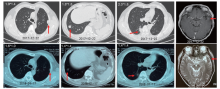

患者于2015年8月来我院门诊, 复阅术前及术后CT, 对比发现双肺结节术前即已存在(术前CT, PET/CT均未报), 予停用吉非替尼。后续定期复查CT, 发现肺内结节逐渐增大。2017年1月行头颅MR提示左侧颞叶结节, 大小约0.7 cm, 考虑转移(见图1)。诊断:左上肺腺癌, cT4N0M1b(双肺、单发脑), Ⅳ A期。